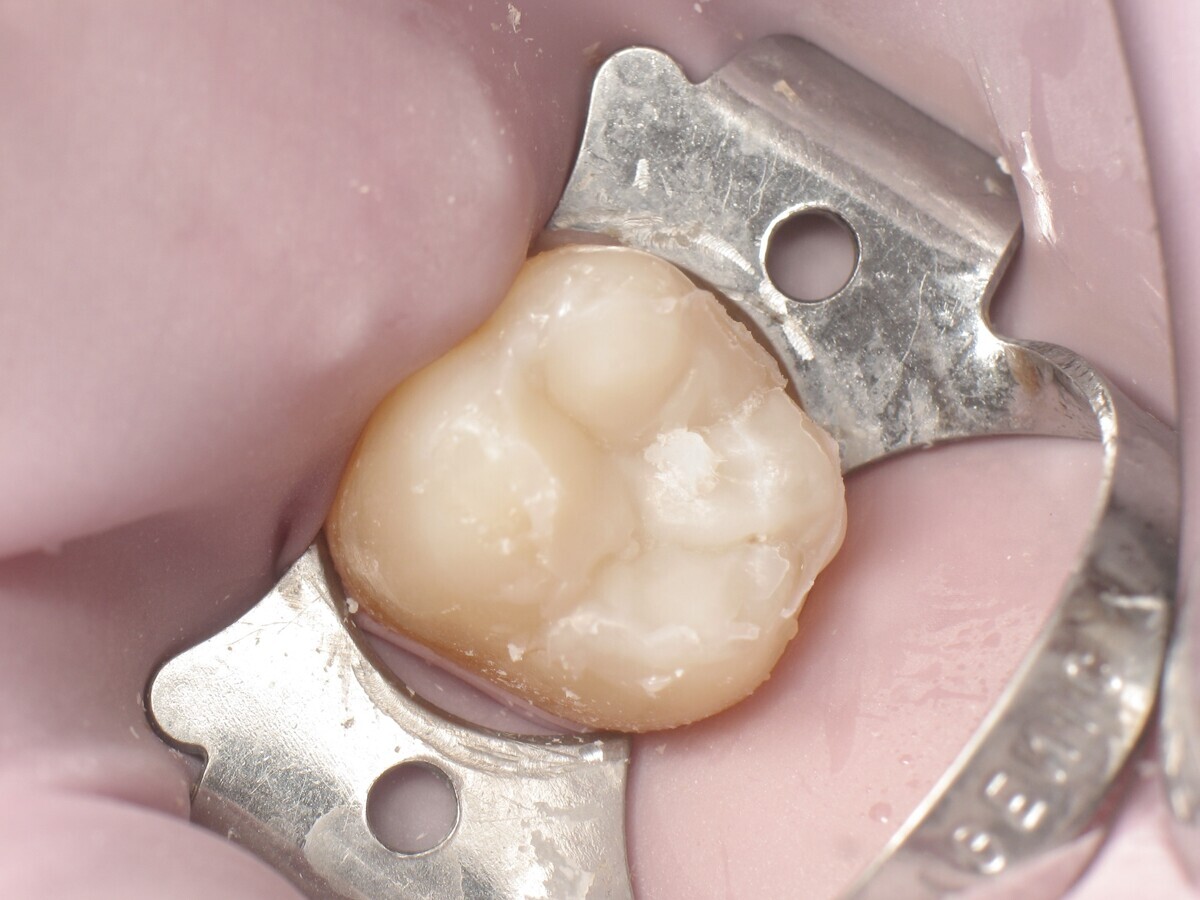

Este artículo describe el tratamiento de una cavidad clase I en un molar utilizando un composite termoviscoso mediante la técnica de la almohadilla (Figura 1). En primer lugar, se registran los detalles anatómicos utilizando una resina transparente, fluida y fotopolimerizable (Clip Flow, VOCO). El diente se aísla con un dique antes de aplicar el composite transparente a la superficie oclusal con un cepillo aplicador y fotopolimerizar durante 10 segundos (Figuras 2-4). La almohadilla oclusal así obtenida (Figura 5) debe almacenarse en alcohol (etanol o isopropanol) para eliminar la capa de inhibición. Luego se limpia la cavidad clase I (Figuras 6 y 7). A continuación se graba el esmalte durante 30 segundos y la dentina durante 15 segundos (Conditioner 36, Dentsply Sirona) y luego se enjuaga bien (Figuras 8 a 10). Debido al bajo espesor de la dentina remanente, también se aplica protección pulpar (Telio Desensitizer, Ivoclar Vivadent) (Figura 11). Luego se frota el adhesivo sobre las superficies dentales durante 20 segundos (Futurabond DC, VOCO), luego se seca bajo una pulverización de aire sin aceite graso durante 5 segundos y luego se fotopolimeriza durante 10 segundos (Figuras 12, 13). Para una humectación óptima, el fondo de la cavidad se cubre con un compuesto fluido de baja viscosidad (GrandioSO Light Flow, A3.5, VOCO) y se fotopolimeriza durante 20 segundos (Figuras 14, 15). Utilizando el Dispensador VisCalor, un dispensador portátil que permite el calentamiento y la aplicación simultánea de resinas, la cavidad se llena luego con un composite termoviscoso bulk (VisCalor Bulk, A2, VOCO).

Figura 12. Cavidad después de la aplicación de Futurabond DC.

Figura 13. Fotopolimerización del adhesivo.